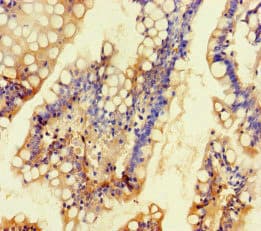

Anti-TALK1 antibody(ab234652)

Rabbit Polyclonal TALK1 antibody. Suitable for IHC-P and reacts with Human samples. Immunogen corresponding to Recombinant Fragment Protein within Human Potassium channel subfamily K member 16 aa 250 to C-terminus.

Applications IHC-P

Species Reactivity Human